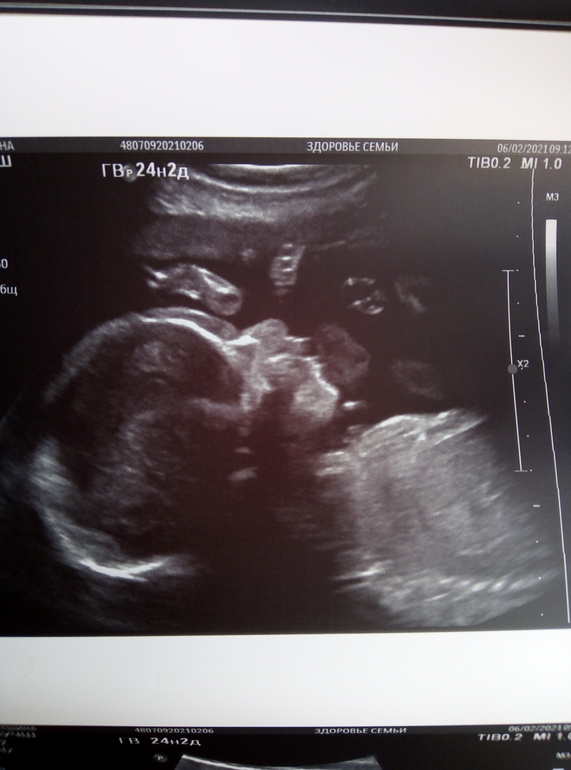

25 НЕДЕЛЬКА фотопуз + УЗИ❤️

Стартовала 25 неделя, как же быстро летит время, сгонял на доплер, заодно посмотрели дочу в 3д, ну и всё остальное быстро глянули, всё хорошо тьфу тьфу, волосы говорит длинные уже у вашей принцессы, я аж удивилась, показала мне прям волосы на голове ёжик такой прям, а фото в 3д боже такой гномик шладкий и тут я поняла что мы вылитый папа))))